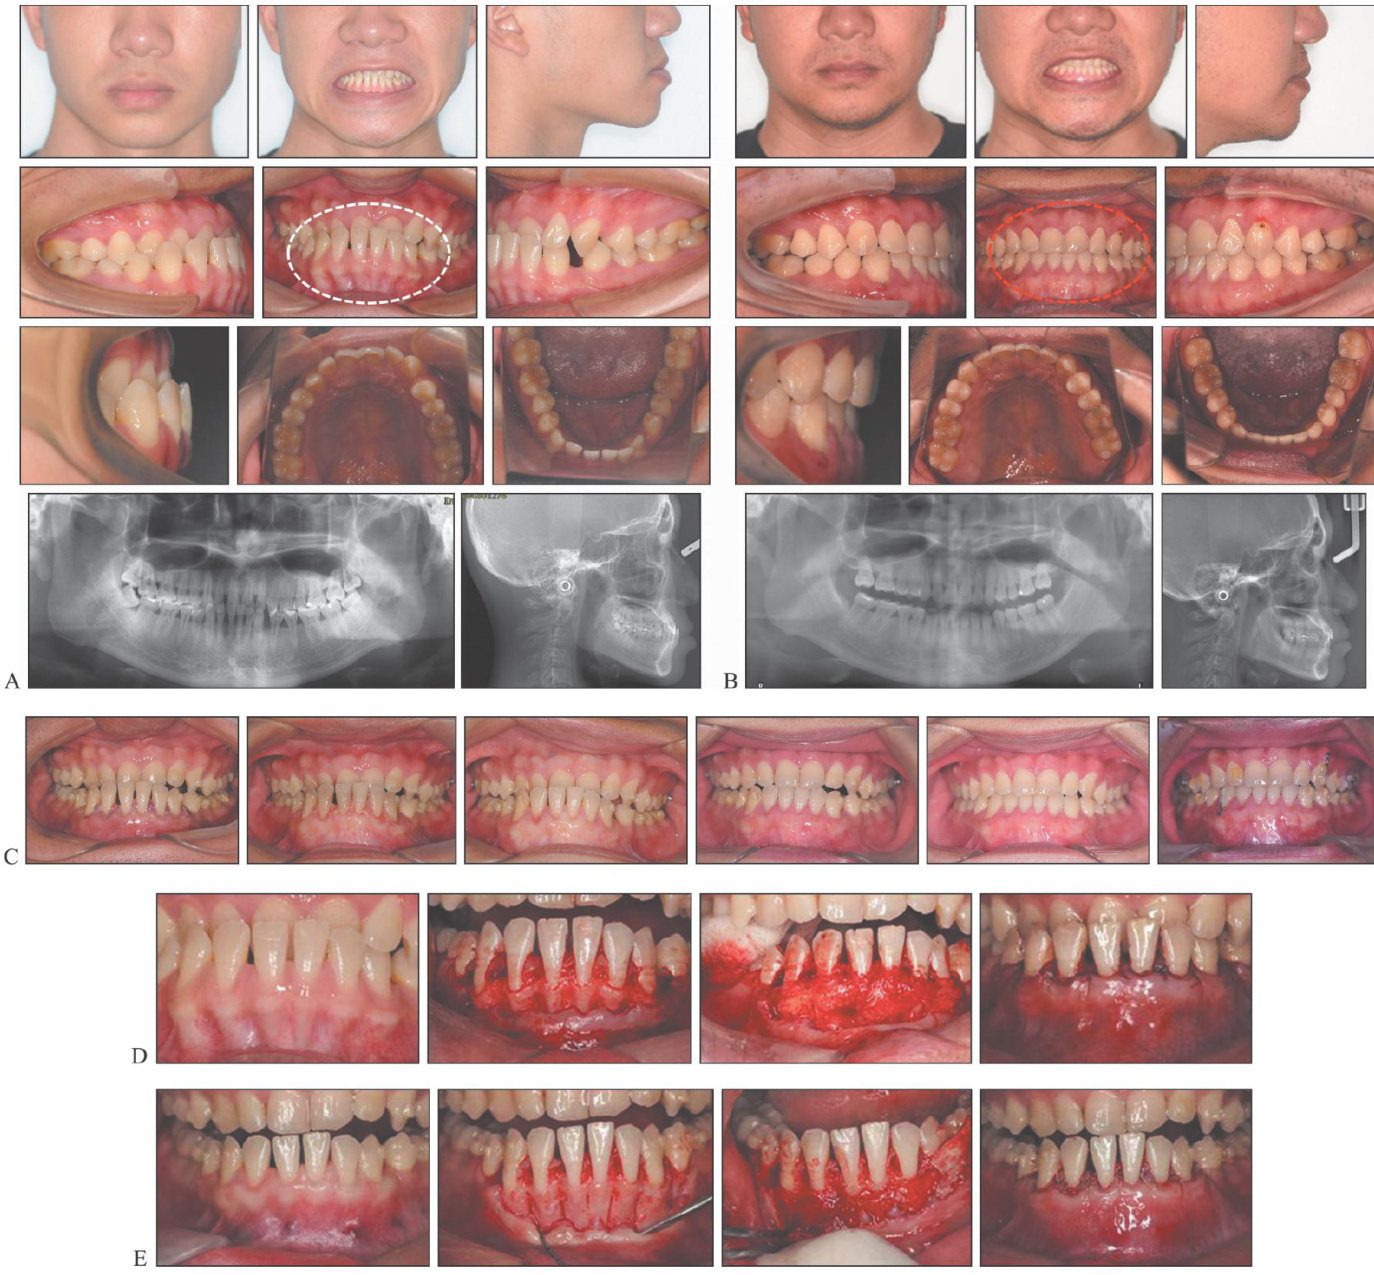

隐形矫治技术在多学科复杂病例中的应用

[Abstract]Clearaligner treatment has evolvedover the last 2O years.Ithas transformed fromasim(剩余13153字)